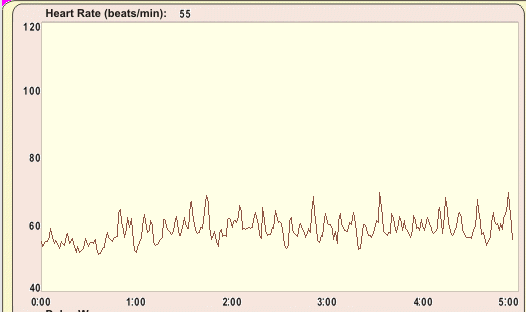

自律神経バランスを測定した結果

Hさんの自律神経バランスを測定したところ、副交感神経の働きが低下し、 自律神経全体がアンバランスな状態でした。 副交感神経がうまく働かないと、身体は常に緊張状態になります。 結果として「回復力が落ち」「痛みを感じやすい脳の状態」になってしまうのです。 つまり、トレイルランニングそのものが原因ではなく、ストレスによって痛みに敏感になっていたのです。

上記の測定結果は、現在は、TAS9VIEWという新しい自律神経バランス測定器での計測になっています